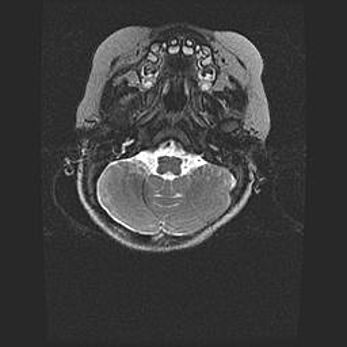

Подострая гематома правой гемисферы мозжечка.

Наружная гидроцефалия.

Возраст: 15 дней

Вес: 3100 г

Пол: женский

Окружность головы: 37 см

Срок гестации: 35-36 недель

При открытой наружной форме гидроцефалии у новорожденных расширяются и переполняются субарахноидные пространства.

Кровоизлияния в мозжечок имеют две клинико-анатомические формы: полушарные гематомы и кровоизлияния в червь.

К появлению этой патологии может привести: повреждения головного мозга, возникающие в результате асфиксии и гипоксии плода при беременности, или травмы во время родов. Редко гематома мозжечка может быть результатом первичной коагулопатии и сосудистой мальформации, диссеминированном внутрисосудистом свертывании, изоиммунной тромбоцитопении.